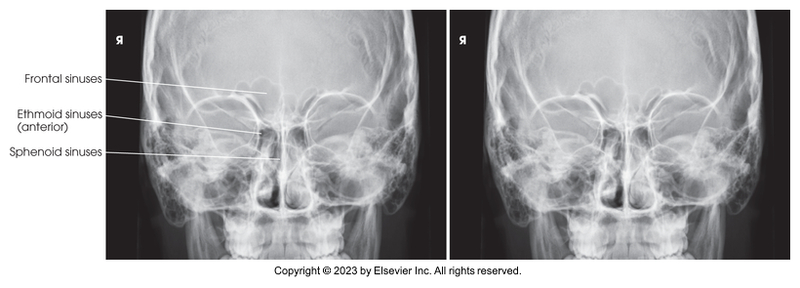

Lateral Projection of Paranasal Sinuses

PA Axial of the Frontal and Ethmoidal Sinuses - Caldwell Method

Submentovertical of Ethmoidal & Sphenoidal Sinuses

Lateral of the sinuses

PA axial of the frontal and ethmoidal sinuses (Caldwell Method)

Submentovertical of the ethmoidal and sphenoidal sinuses